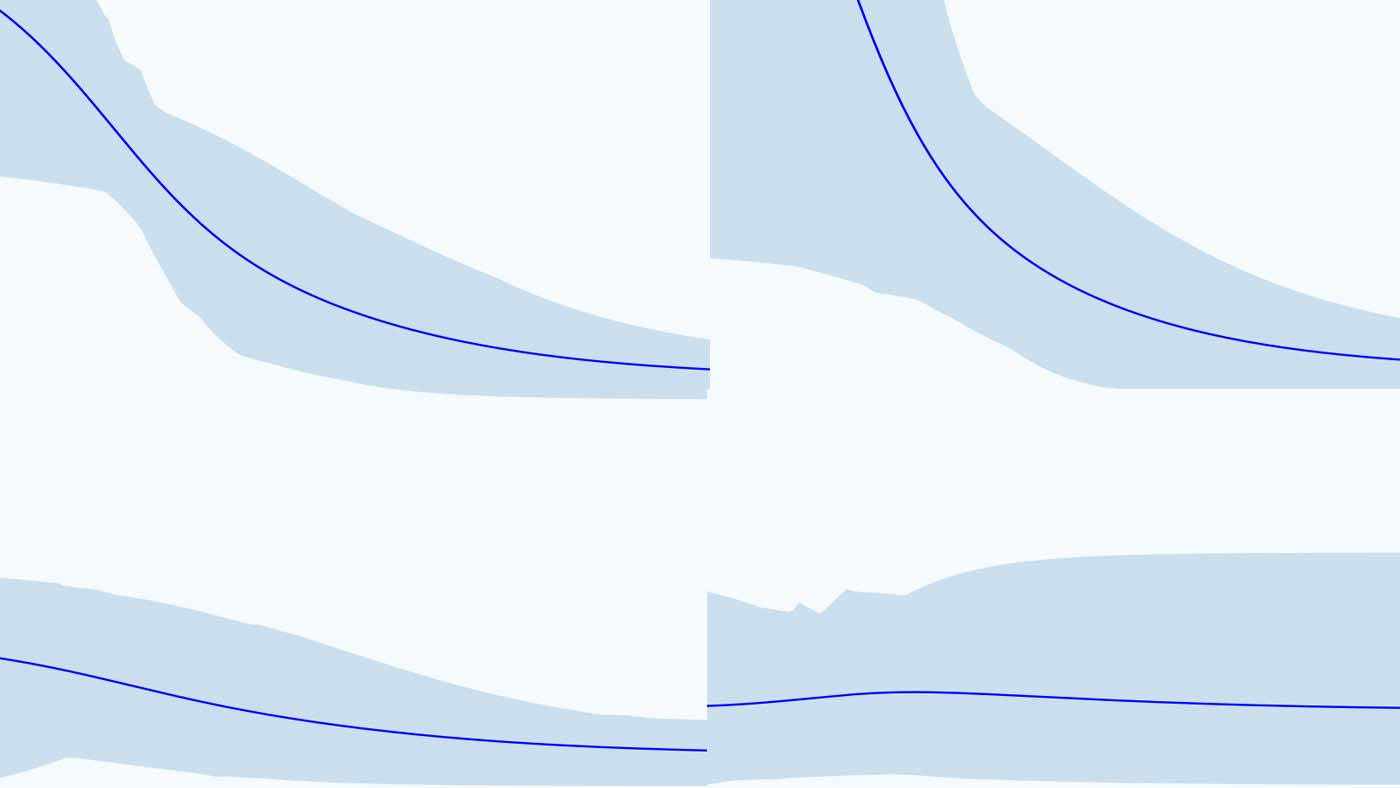

Supporting clinicians to assess COVID-19 severity using AI and Chest X-rays

Removing biases from deep learning-based models of COVID-19 chest X-rays